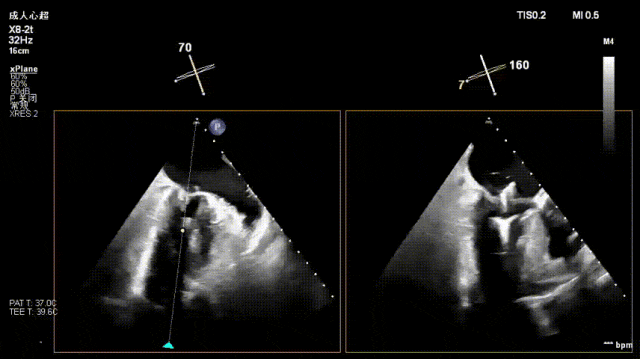

术前经食道超声显示:二尖瓣C1、P1区脱垂,重度关闭不全,彩色多普勒提示大量二尖瓣反流。术前瓣口面积MVA约5cm²,瓣环前后径AP约36.9mm,前叶A1约26mm,后叶P1约15.2mm。